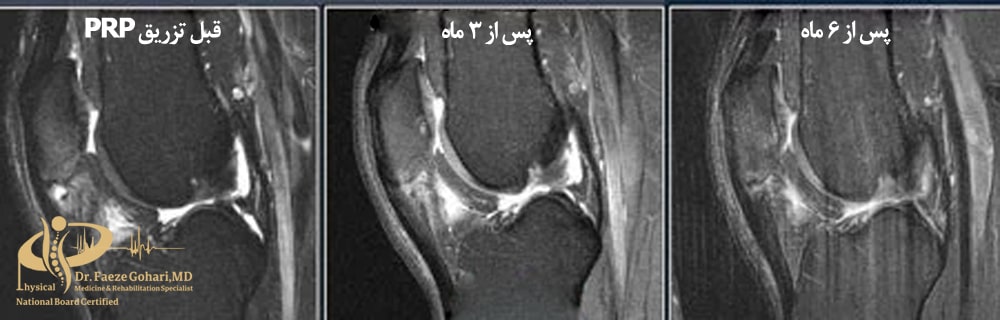

تصویر A قبل از پی ار پی – تصویر B یکسال پس از پی ار پی (کاهش قابلتوجه آسیب غضروفی در بیمار ۶۷ساله)